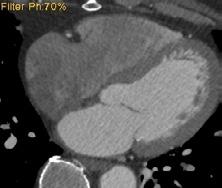

Imagistica cardiacă – rol, metode și perspective

Conf. Univ. Dr. Bogdan Popa